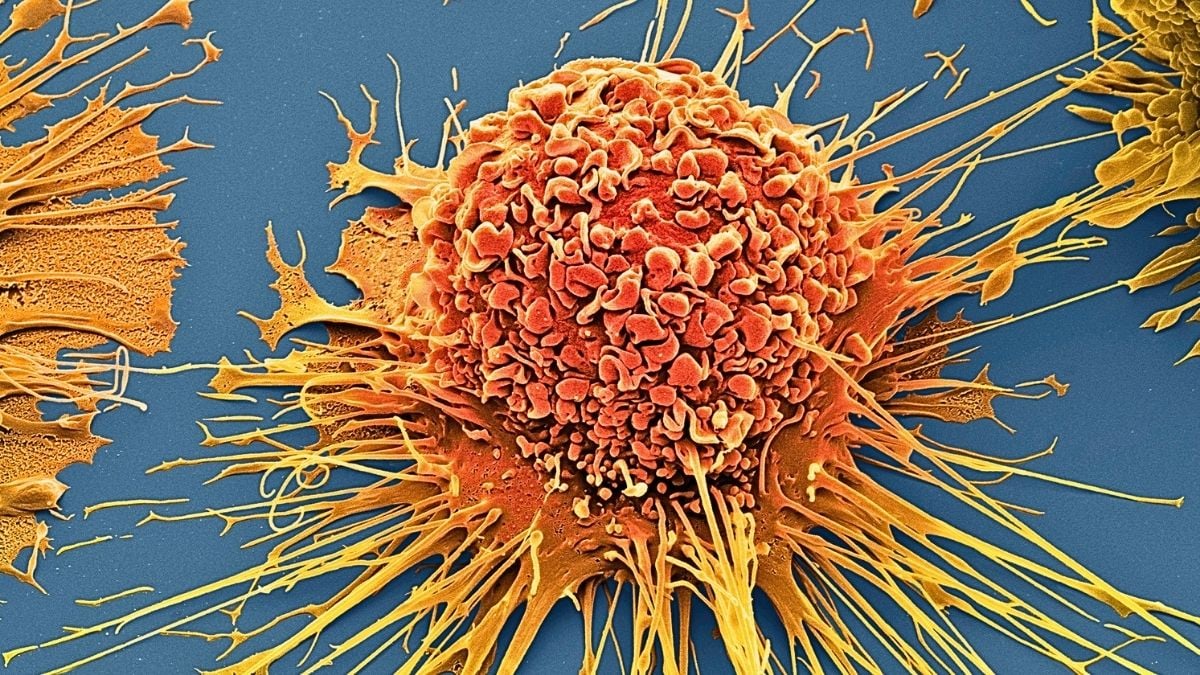

Una dintre provocările majore este că nu putem testa cu ușurință cum va reacționa o inimă umană la un medicament sau boală fără a pune pe cineva în pericol. Această țesută cardiacă inginerizată bate de una singură, mobilizează calciu pentru a iniția activitatea musculară și răspunde previzibil la medicamente comune. Este prima care incorporează o…